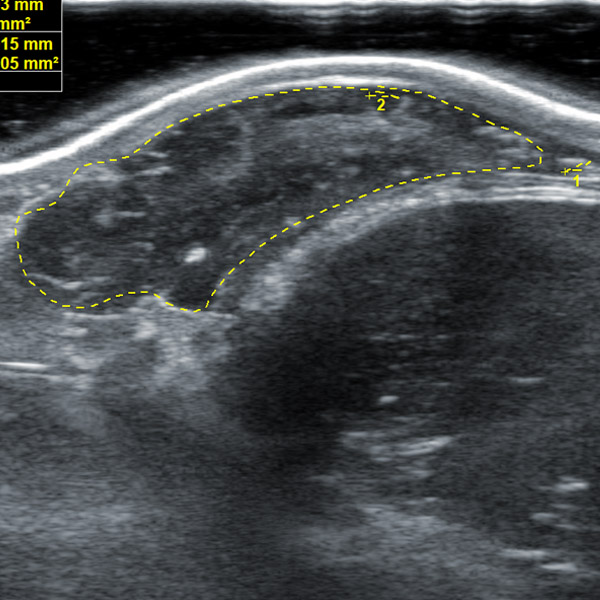

1.30. Image editing: Stored images can be edited. Stored videos can be edited for each frame

1.31. When measuring animal back fat, the back fat measurement and eye muscle depth can be adjusted to be on the same line

1.23. Built-in professional back fat eye muscle storage image system, can store back fat eye muscle images according to different parts of different animals for inspection

1. 18cm long professionally designed backfat eye muscle probe, which can fully test the backfat eye muscles of various animals

2. The probe scanning depth can reach 30cm, which can well present the eye muscles of large animals

3. High-frequency probe and high-quality Doppler color ultrasound images can well identify the measured muscle quality grade